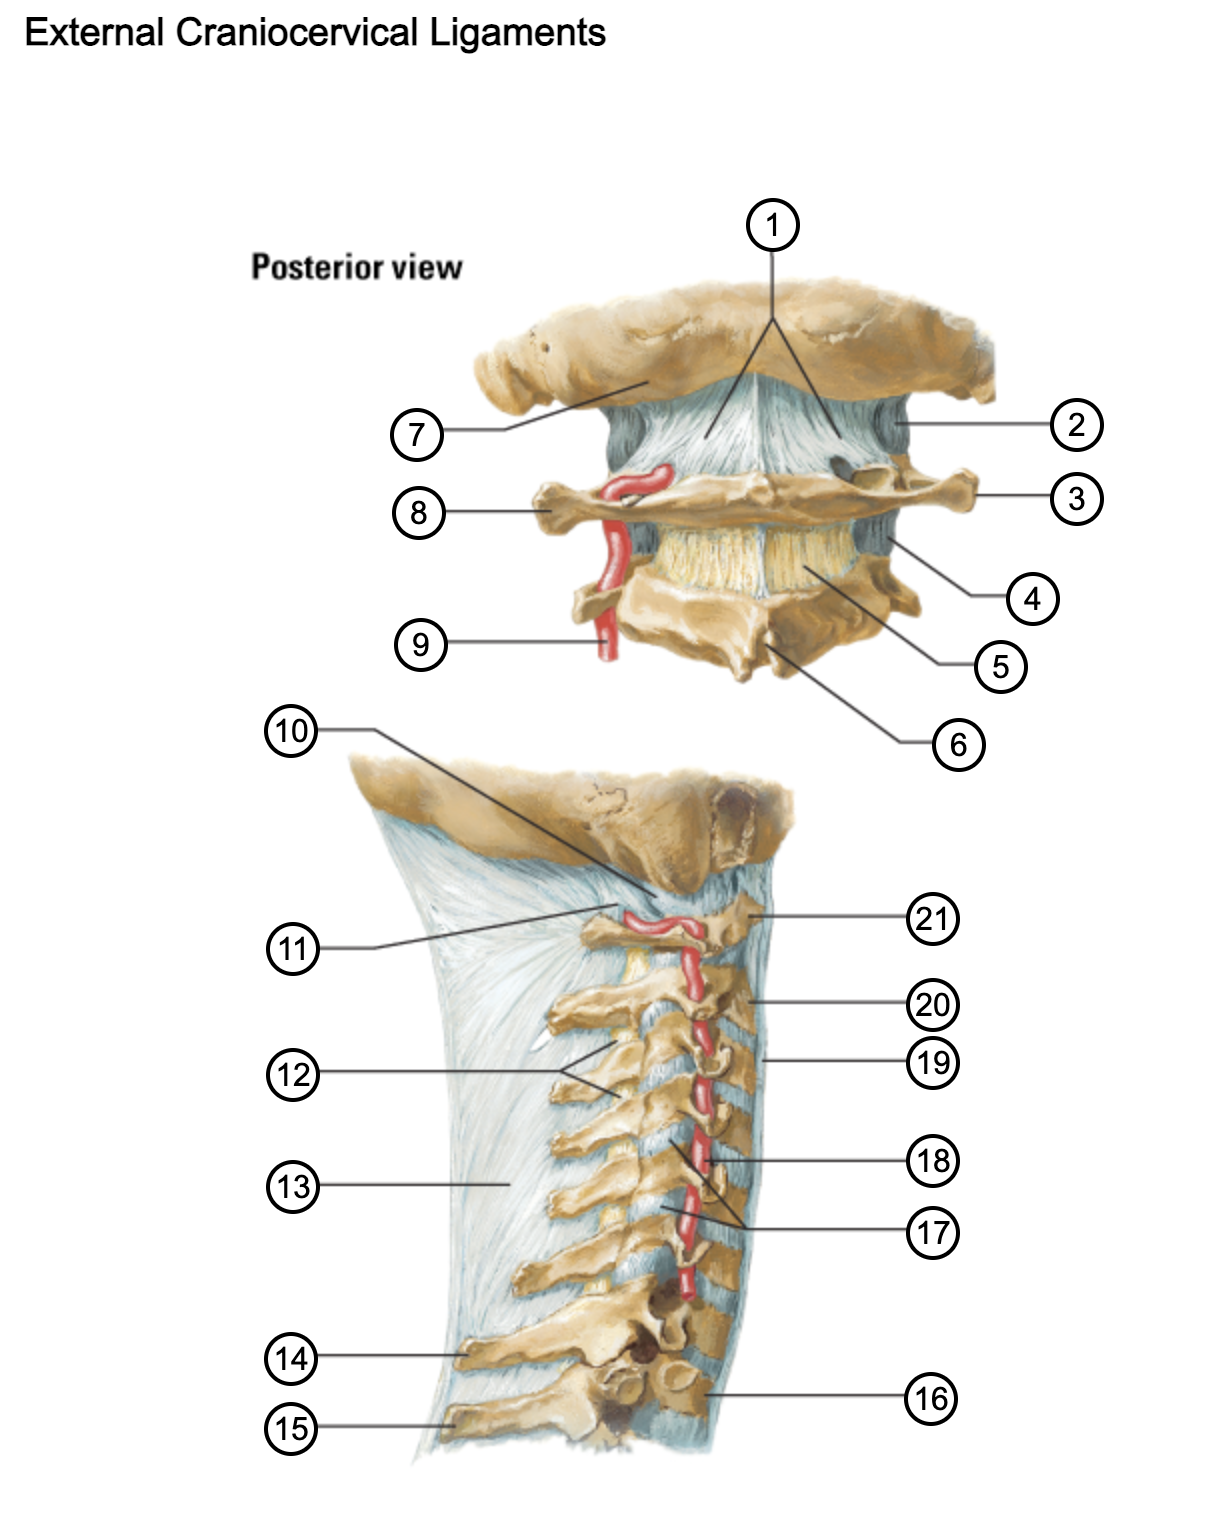

1

posterior antlantooccipital membrane

2

capsule of atlantooccipital joint

3

transverse process of atlas (C1)

4

capsule of lateral atlantoaxial joint

5

ligamenta flava

6

spinous process

7

occipital bone

8

transverse process of atlas (C1)

9

vertebral artery

10

capsule of atlantooccipital membrane

11

posterior atlantooccipital membrane

12

ligamenta flava

13

nuchal ligament

14

spinous process of C7 vertebra

15

spinous process of T1 vertebra

16

T1 vertebra

17

zygapophysical joints (C4-5 and C5-6)

18

vertebral artery

19

anterior longitudinal ligament

20

body of axis

21

Atlas (C1)